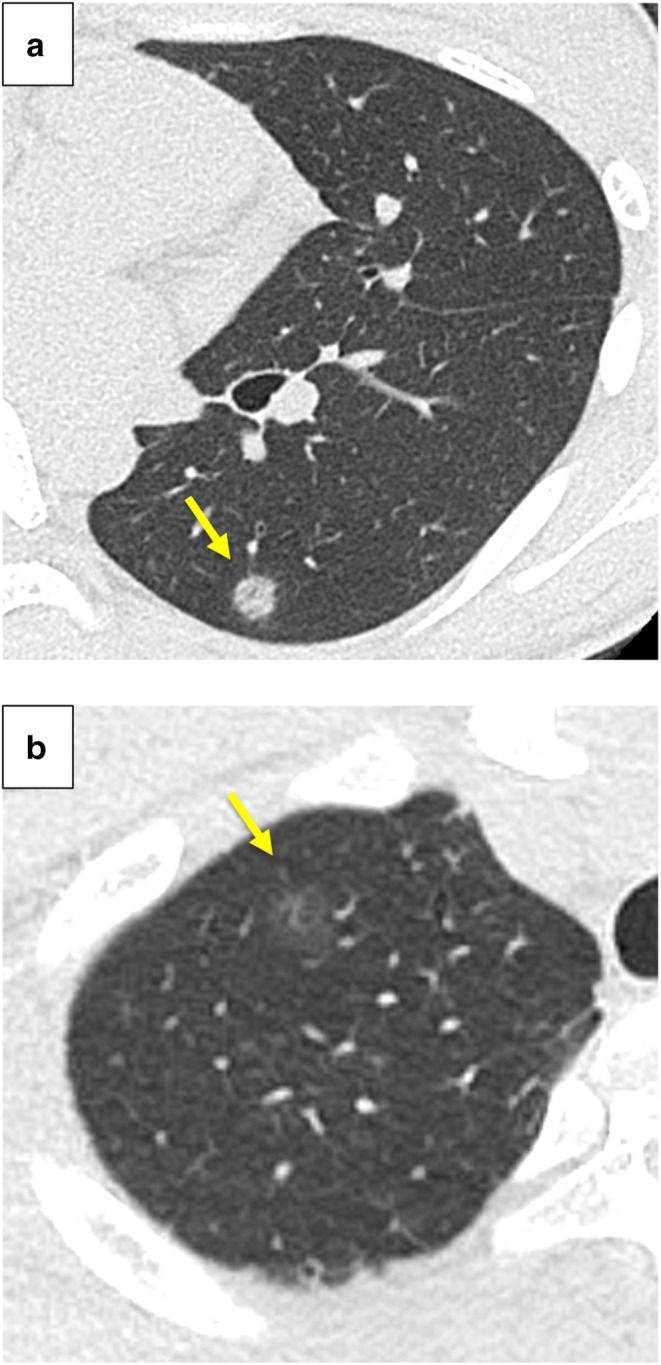

We experienced two cases of lung cancer in teenagers. Case 1 involved a 17-year-old never-smoking girl with no medical history. Chest computed tomography revealed a 9 × 7 mm ground-glass nodule in the left lung. Case 2 involved an 18-year-old man with no smoking history but bilateral pneumothorax. Chest computed tomography showed a 13 × 11 mm ground-glass nodule in the right lung. In both cases, thoracoscopic wedge resection was performed, and the tumours were pathologically diagnosed as adenocarcinoma in situ. There was no evidence of recurrence for 2 years in Case 1, and for 1.5 years in Case 2.